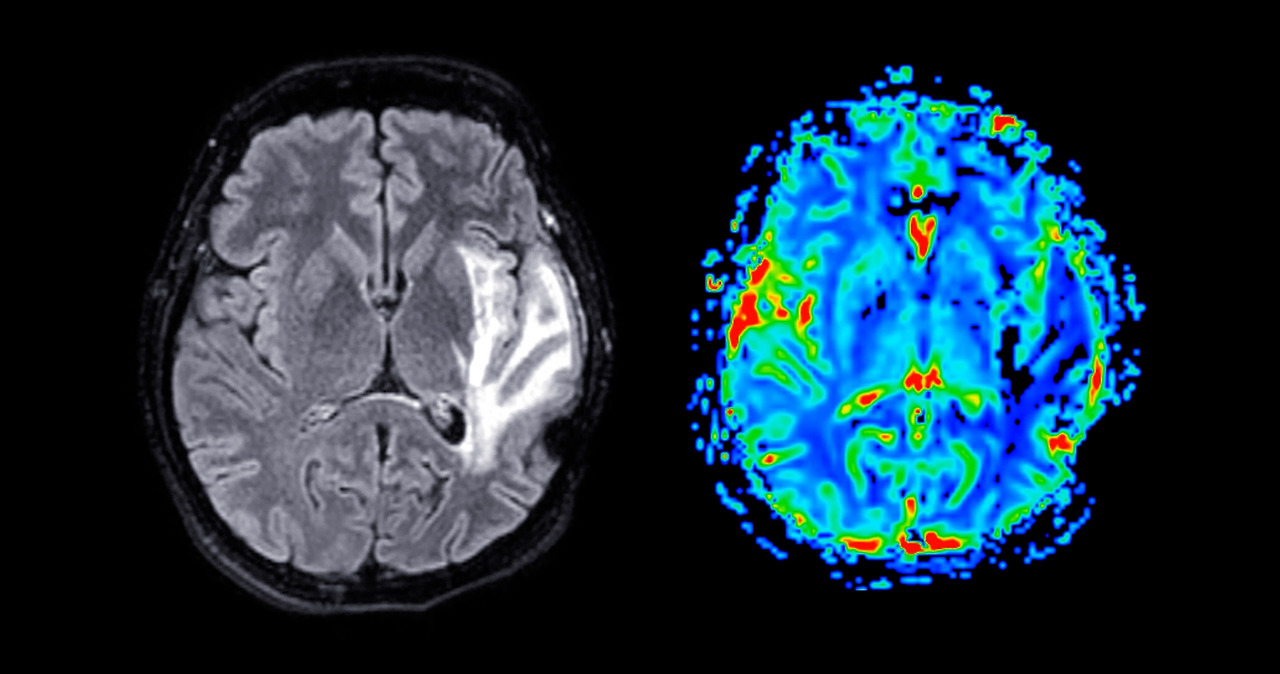

첫째, 하나의 검사는 모든 것을 보여주지 못합니다.

MRI는 구조를 봅니다.

뇌파 검사는 검사하는 순간의 뇌의 전기 신호를 봅니다.

유전자 검사는 확진이 되기도 하지만, 가능성을 말하기도 합니다.

각각의 검사는 서로 다른 질문에 답할 뿐,

이 아이가 앞으로 괜찮을지 라는 질문에는 직접 답하지 않습니다.